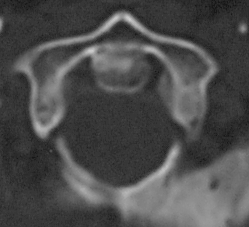

Koronal BT Kesiti - Os Odontoideum Aksiyal BT Kesiti - Atlas Füzyonu

Resim 3: Koronal BT kesidinde (sol) densin sklerotik kenarlarla ayrı bir kemik haline gelerek (=os odontoideum) C2 gövdesinden ayrışmış olduğu görülmektedir. Aksiyal BT kesidinde (sağ) os odontoideum'un atlas ön arkusuna kaynamış olduğu görülmektedir.